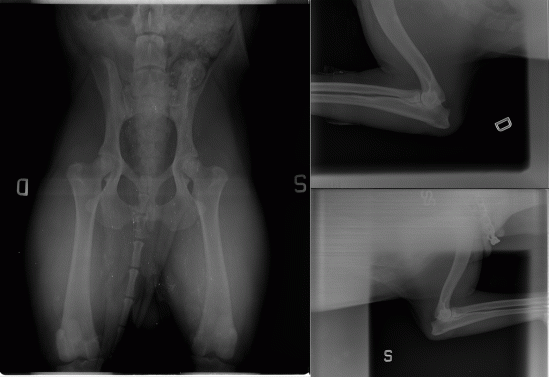

HDB – ED0

COD AJAHMW1Z – PW QJ4K5

Inka X-Ray page @ Celemasche

COD. XAMGXKRS- PW. I1FHH